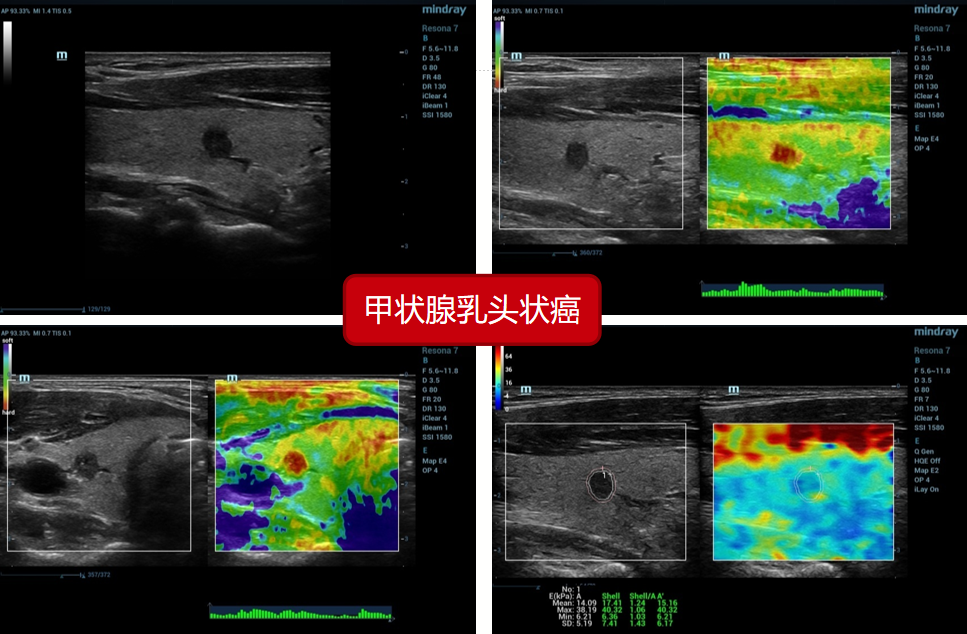

2、甲状腺乳头状癌(病例来源上海六院):

2、甲状腺乳头状癌(病例来源上海六院):